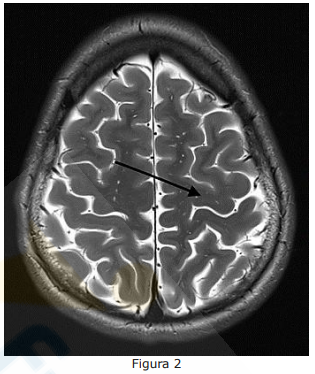

Na Figura 2 abaixo, qual é a área do cérebro destacada pela seta?